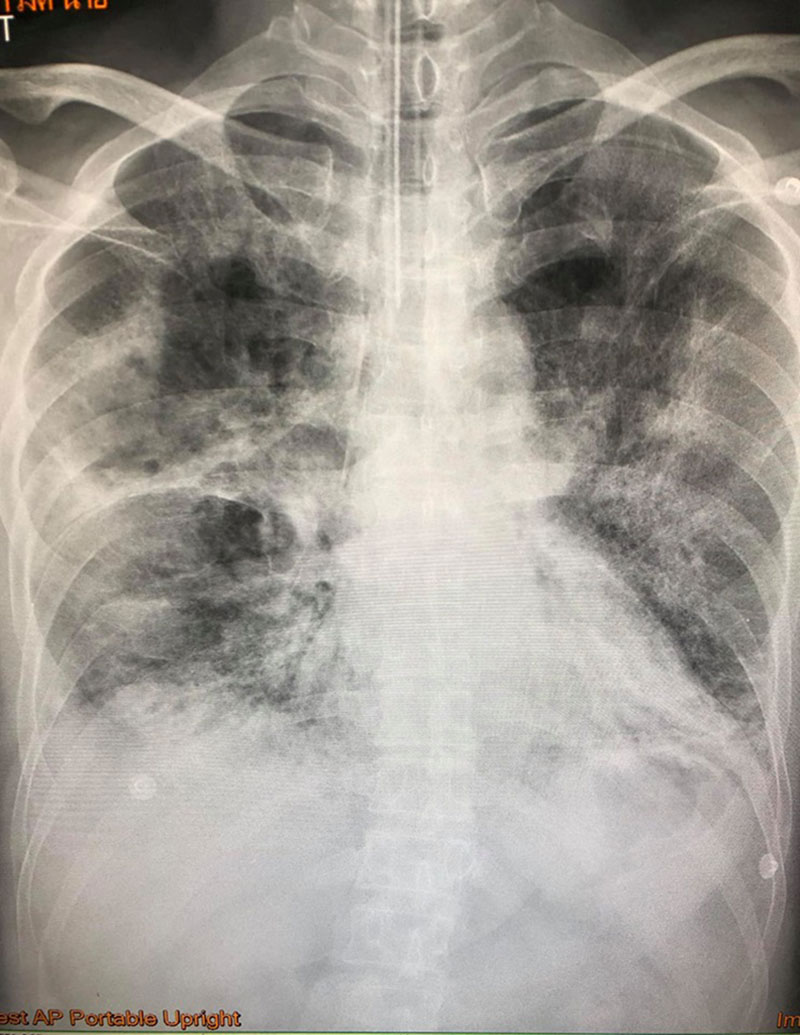

ต่อมา ชายคนดังกล่าว ได้เข้ารับการรักษาในโรงพยาบาล และเมื่อเอกซเรย์ปอดก็พบว่า ปอดทั้ง 2 ข้างผิดปกติ ระดับออกซิเจนในเลือดต่ำมาก แต่คลื่นหัวใจปกติ เมื่อตรวจหาเชื้อไข้หวัดใหญ่ในช่องจมูกแบบเร็ว ผลออกมาเป็นลบ แพทย์จึงสั่งให้ยารักษาไข้หวัดใหญ่ Tamiflu กินจนครบ 5 วัน ให้ยาปฏิชีวนะ และยาสเตียรอยด์

อย่างไรก็ตาม อาการของผู้ป่วยไม่ดีขึ้น ซ้ำยังต้องให้ออกซิเจนตลอดเวลา จึงทำการเอกซเรย์ปอดอีกครั้ง และพบว่า ปอดด้านซ้ายผิดปกติมากกว่าด้านขวา และปอดข้างขวารั่ว 15%